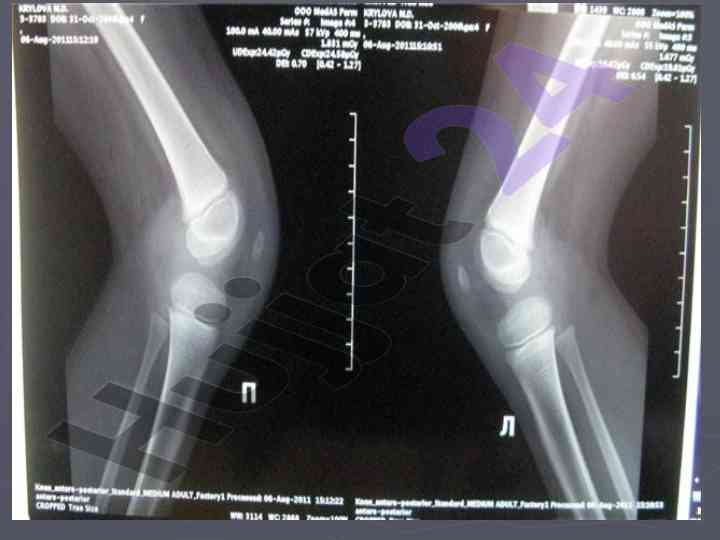

Bolalarda suyak tizimining xususiyatlari va siniqlar

Bolalarda suyak tizimining xususiyatlari, suyaklarni sanchish turlari va regeneratsiya jarayonlari, diagnostika va usish zonalari haqida ma'lumot.